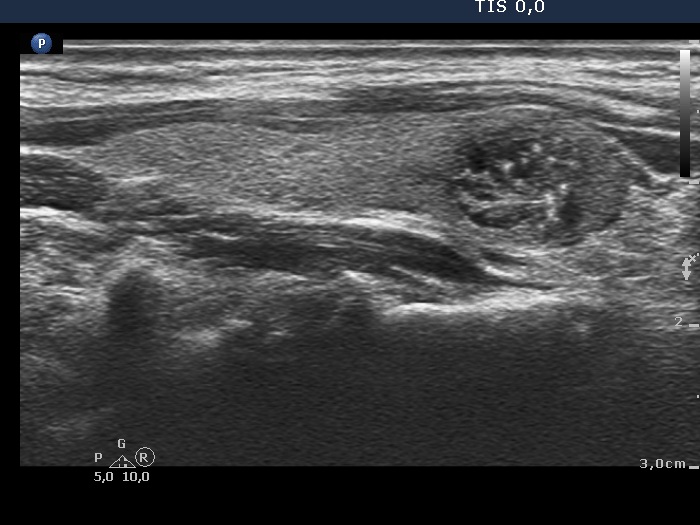

TIRADS - case 2166 (ultrasonographic picture 7)

Right lobe, longitudinal scan, enlargement.